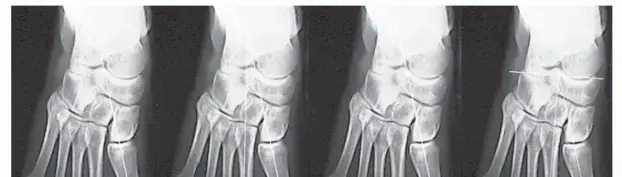

1. الأشعة السينية (X-rays):

• هي الخطوة الأولى والأكثر أهمية في التشخيص.

• تُظهر الأشعة السينية النتوء العظمي بوضوح كبروز عظمي يمتد من سطح العظم، ويكون نخاع النتوء متواصلاً مع نخاع العظم الأم.

• يمكنها تحديد حجم النتوء، موقعه، وشكله (معنق Pedunculated أو قاعدي Sessile).

• تساعد في تقييم أي تشوهات عظمية مصاحبة، خاصة في حالات HME.

• تظهر القلنسوة الغضروفية عادة شفافة في الأشعة السينية ولا يمكن رؤيتها مباشرة.